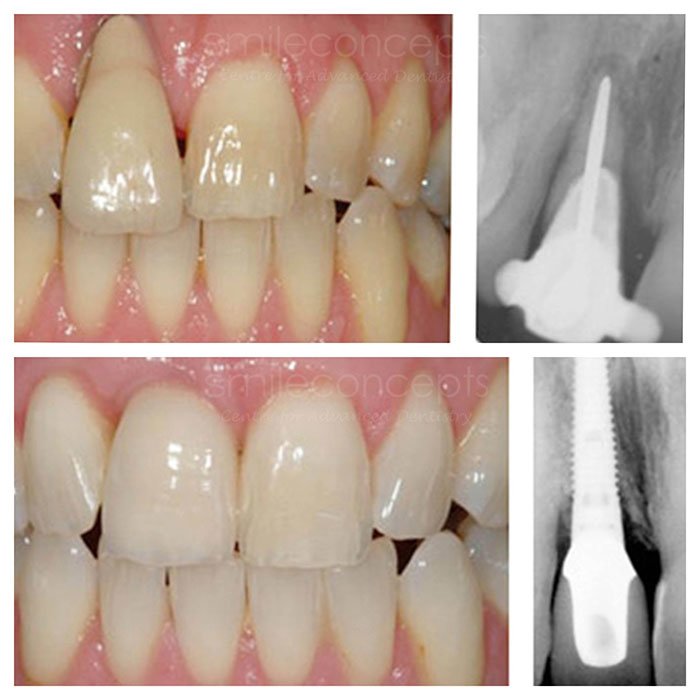

SMILE TRANSFORMATION